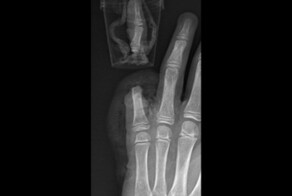

62-летний мужчина получил травму на производстве - произошла ампутация всех 5 пальцев. Пациент обратился в Центр Микрохирургии кисти ГКБ им. Ерамишанцева в Москве.

Врачами было принято решение разделить операцию на два этапа: сначала восстановить ампутированный блок из 4 пальцев, а уже на втором этапе реплантировать первый палец, который был сразу помещен в холодильник с температурой 4 градуса Цельсия.

Операцию начал врач-хирург Александр Тимофеевич Сухинин с операционной медицинской сестрой Измайловой Гулнарой Джанжигитовной. В процессе был выполнен остеосинтез костей спицами, чтобы зафиксировать положение ампутированных пальцев, также были сшиты сухожилия сгибателей и разгибателей пальцев. На микрохирургическом этапе были сшиты вены и артерии, обеспечивающие приток и отток крови в пальцах и восстановлены пальцевые нервы для возвращения чувствительности в пришитых пальцах.

Александр Тимофеевич оперировал 10 часов, после чего его сменил Артем Ильдарович Шакиров, который в течение 4 часов занимался реплантацией большого пальца.

"Операция прошла успешно: все пальцы прижились полностью и без осложнений. Пациент выписан из отделения спустя неделю: мы сделали все, чтобы после реабилитационного периода кисть с реплантированными пальцами восстановила функции, и пациент мог вернуться к привычному образу жизни" - прокомментировал руководитель Центра микрохирургии кисти Георгий Адольфович Назарян.